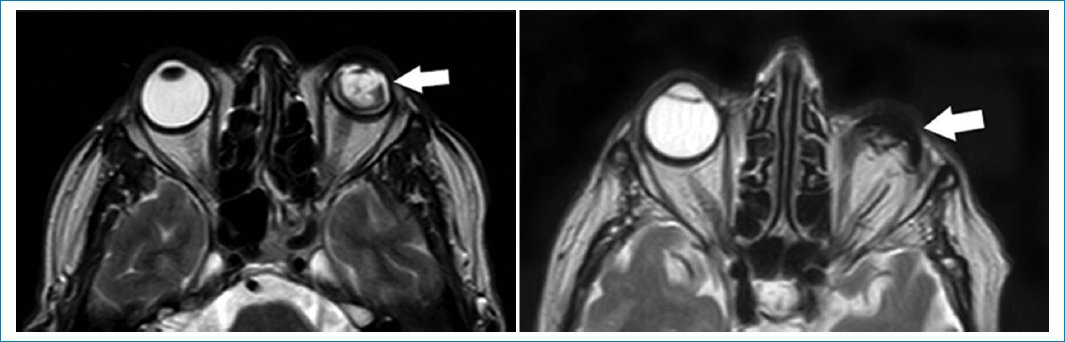

La ptisis bulbi es la atrofia, asociada a calcificaciones, del globo ocular, secundaria a traumatismo o procesos infecciosos/inflamatorios previos26.

El globo ocular se aprecia heterogéneo, tanto en secuencias ponderadas en T1 como T2, con calcificaciones groseras asociadas. No es necesaria la administración de gadolinio (Fig. 7)27.

Figura 7. Imágenes potenciadas en T2. Cortes axiales. Se aprecia alteración y deformación del globo ocular, compatible con ptisis bulbi (flechas).

Los quistes simples dentro de las glándulas lagrimales son conocidos como dacriops28. Se producen por obstrucción de los conductillos glandulares. El antecedente de procesos infecciosos o traumatismos suele estar presente28. En TC se aprecian como masas hipodensas, mientras que en RM se ven hipointensos en T1 e hiperintensos en T2. Con contraste realzan periféricamente (Fig. 8)28.

Figura 8. Quiste de glándula lagrimal izquierda. Cortes axiales, secuencias: T1 (A), T2 (B) y T1 con gadolinio (C). Se aprecia (flechas) una formación quística, hipointensa en T1, hiperintensa en T2, realzando periféricamente con gadolinio, compatible con contenido líquido.